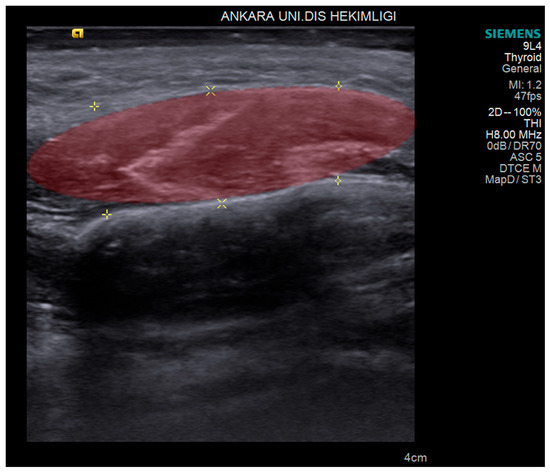

2.2. USG Imaging

2.3. USG Image Segmentation